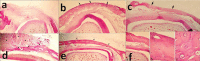

Fig. 6

Histopathological evaluation of the bone samples 4 weeks after surgery: a) the control defect; x60), b) the defect was filled by fibrin glue alone; x60, c) the defect was filled by autologous bone graft; x150. At the 8th week post-surgery: d) formation of a thin cortical bone bridge in control group, while fibrous-immature bone tissue is still presence; x60, e) A complete cortical bone formation that is thicker than 4 weeks post-treatment in fibrin glue group; x60, f) Lamellar bone with less Haversian system in autologous bone graft group; f-a) x150, f-b) x600, f-c) x600 (H&E).